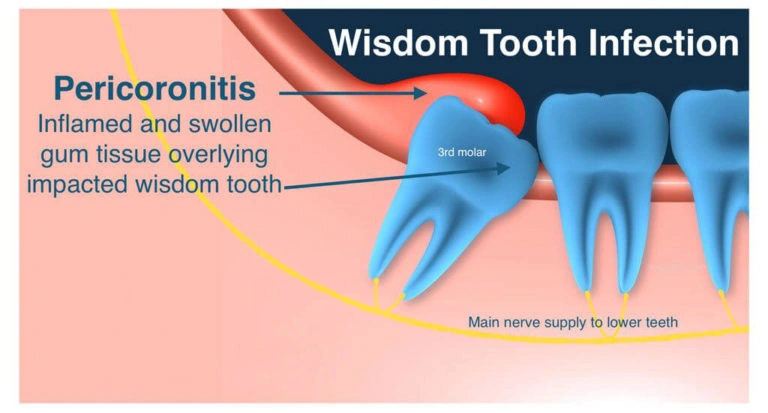

Wisdom teeth are also known as third molars. They usually start coming in between the ages of 17 to 21. They may become impacted if there is not enough space in your mouth for them to erupt fully. A wisdom tooth becomes impacted when it is blocked from pushing through the gums into your mouth. Wisdom teeth can also sometimes come in sideways or be tilted.

However, the gums covering part of or the entire impacted tooth can become infected causing swelling and pain. This is called pericoronitis. Sometimes you might even feel pain in your ear from an impacted wisdom tooth. The infection can spread down your throat or into your neck requiring you to be admitted to the hospital. An impacted tooth can sometimes get a cavity or cause a cavity on the tooth in front of it.